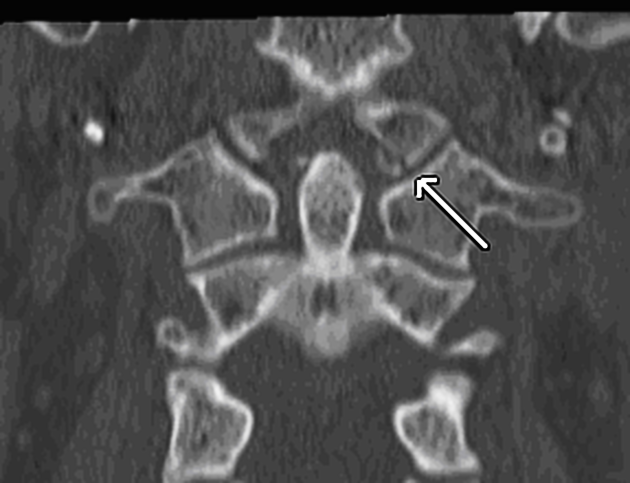

dural AVF

Spinal DAVF will have no flow voids in the cord itself, with have funky serpentine vessels surrounding the cord

spinal avm

notice the flow voids in the spiral cord. Spinal DAVF will have no flow voids in the cord itself, with have funky serpentine vessels surrounding the cord